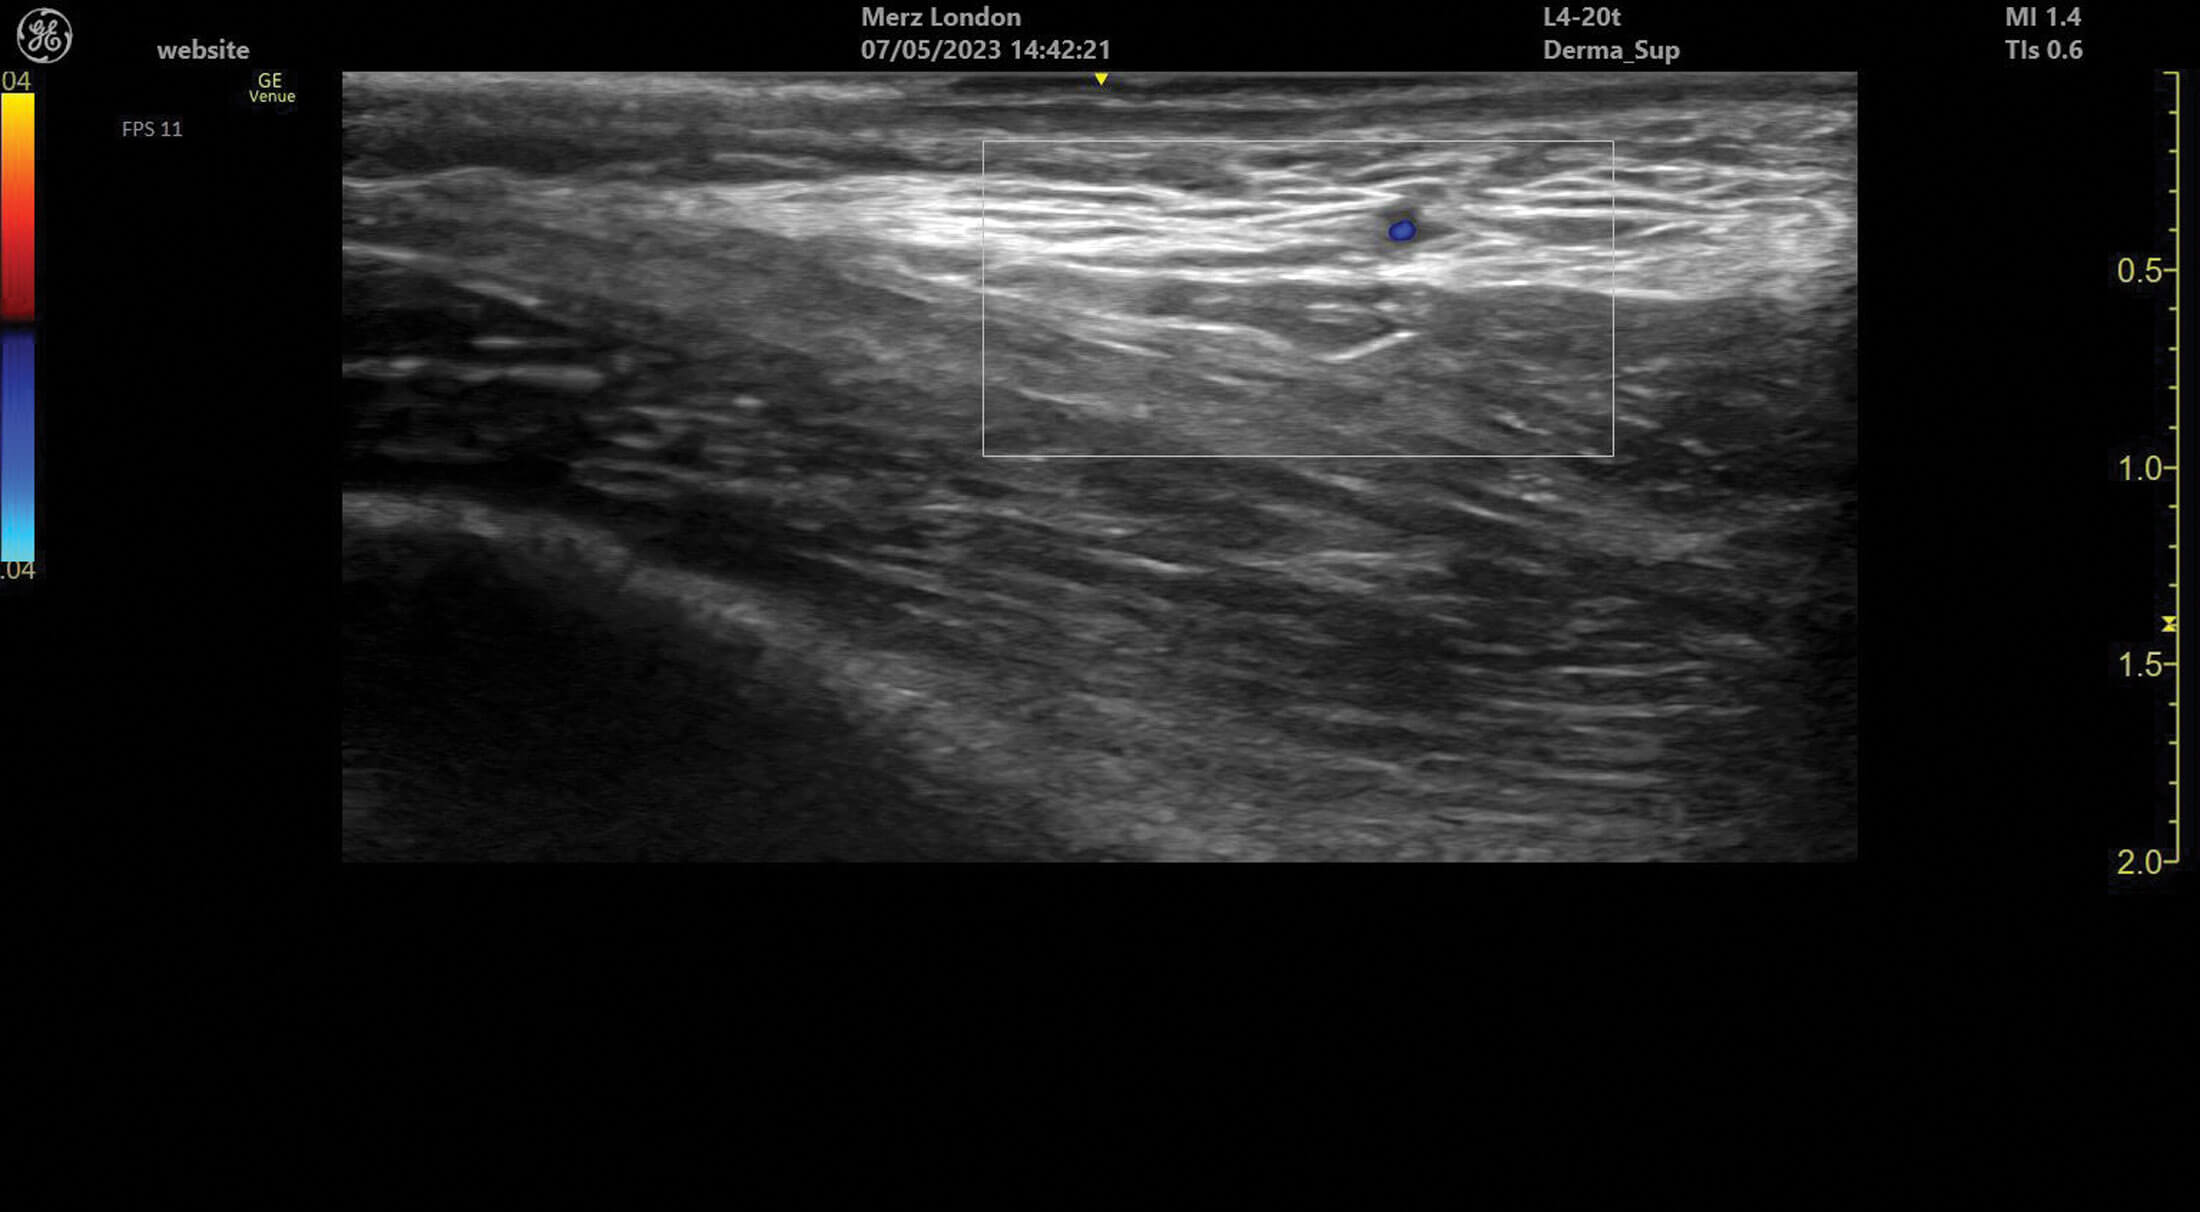

Figure 3: A branch of the superficial temporal artery in superficial tissues of the temple.

Ultrasound doppler can be used to assess blood vessel flow prior to treatments but can also help identify abnormalities in blood supply after filler treatment. Vessels can be identified and tracked in the tissue allowing for the observation of any anatomical variation. Blood vessels always appear as anechoic structures on ultrasound but, when using a colour doppler, flow can be detected either towards (red) or away (blue) from the ultrasound probe [1].